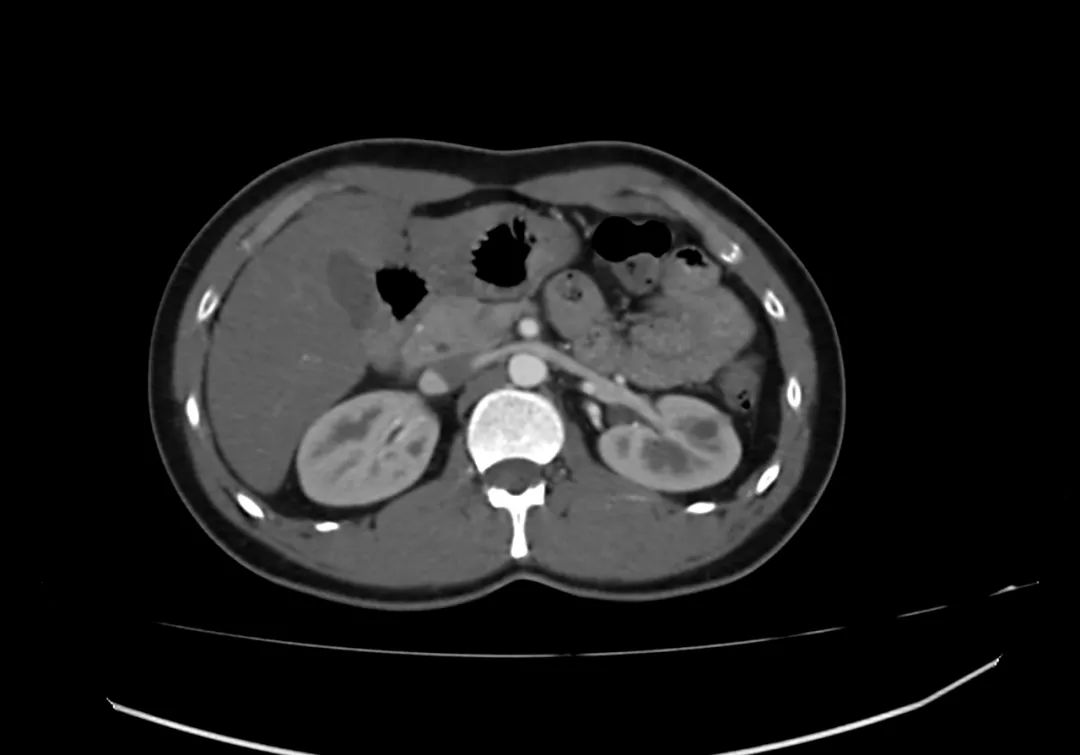

动脉期上腹部轴向增强图像显示胰腺完全包围十二指肠第二部,与完全性环状胰腺一致。

带注释的动脉期图像显示增强胰腺实质(标记为P)完全包裹十二指肠(标记为D)。